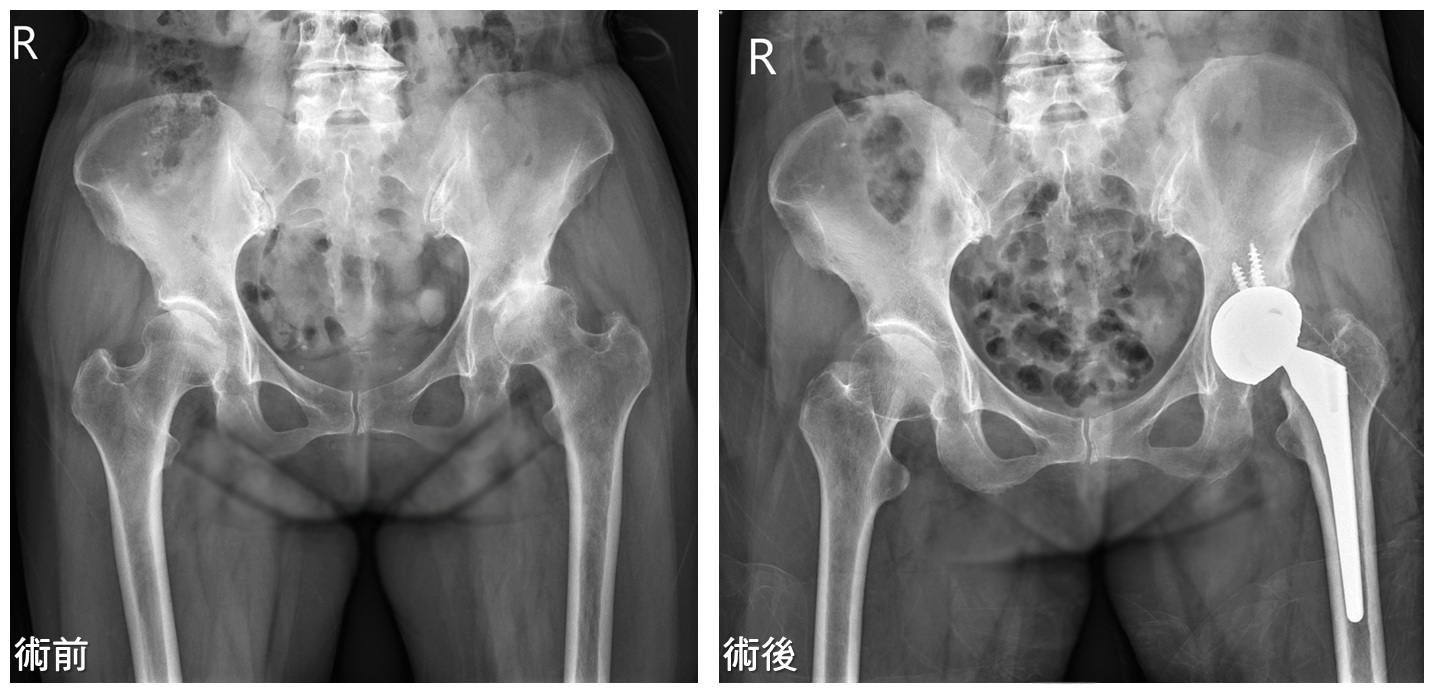

▎案例分享

67歲女性,因左側大腿行走疼痛,今年3月到門診就醫。檢查後發現,左側髖關節有初期退化性髖關節炎,當時先採保守治療,以藥物控制配合熱敷、適當的運動,持續門診追蹤治療,維持還不錯的活動。

但到8月,患者左側髖部疼痛加劇,止痛藥藥效一過,即痛到無法正常行走;回門診追蹤髖部X光,發現關節炎情形惡化,髖關節縫隙摩損嚴重。經過詳細解說病情及充分討論,於9月中旬進行人工髖關節置換手術,使用雙動式超耐磨人工髖關節系統,去除病人疼痛並恢復其日常活動的能力。目前患者復原情形良好,10月初回診時,傷口癒合良好,行走良好無礙,重拾活力與生活品質。